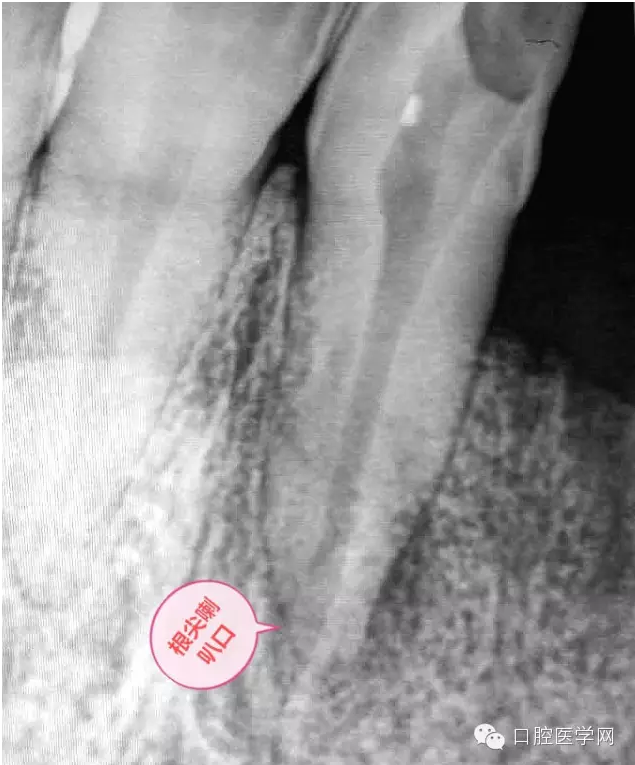

患牙有嚴(yán)重叩診不適。根尖片明確的顯示了牙根根尖喇叭口及根尖均有低密度影像。2年前有外傷史,右上側(cè)切牙缺失。